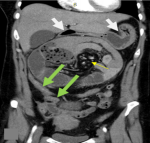

Diagnostic assessment: i) X-ray: plain abdominal radiography demonstrated small bowel air-fluid levels predominantly in the right mesogastric region, without pneumoperitoneum (Figure 1); ii) computed tomography (CT) scan: contrast-enhanced CT confirmed small bowel obstruction due to an internal hernia, with features suggestive of a right paraduodenal hernia (Figure 2-5); iii) laboratory tests: laboratory tests showed leukocytosis with a white blood cell (WBC) count of 12,400/mm3, while liver and kidney function tests, pancreatic enzymes, ionogram, C-reactive protein (CRP), and coagulation profile were all normal.

Figure 2: coronal reformat images: distended centrally located jejunal bowel loops with air fluid levels confirming small bowel obstruction. The stomach and pylorus are superiorly displaced effaced against the hepatic hilum (white arrow)

Figure 5: A,B) show internal hernia containing jejunal bowel loops just beyond the duodenojejunal junction with transition point noted at the white arrow head to the right of the spine